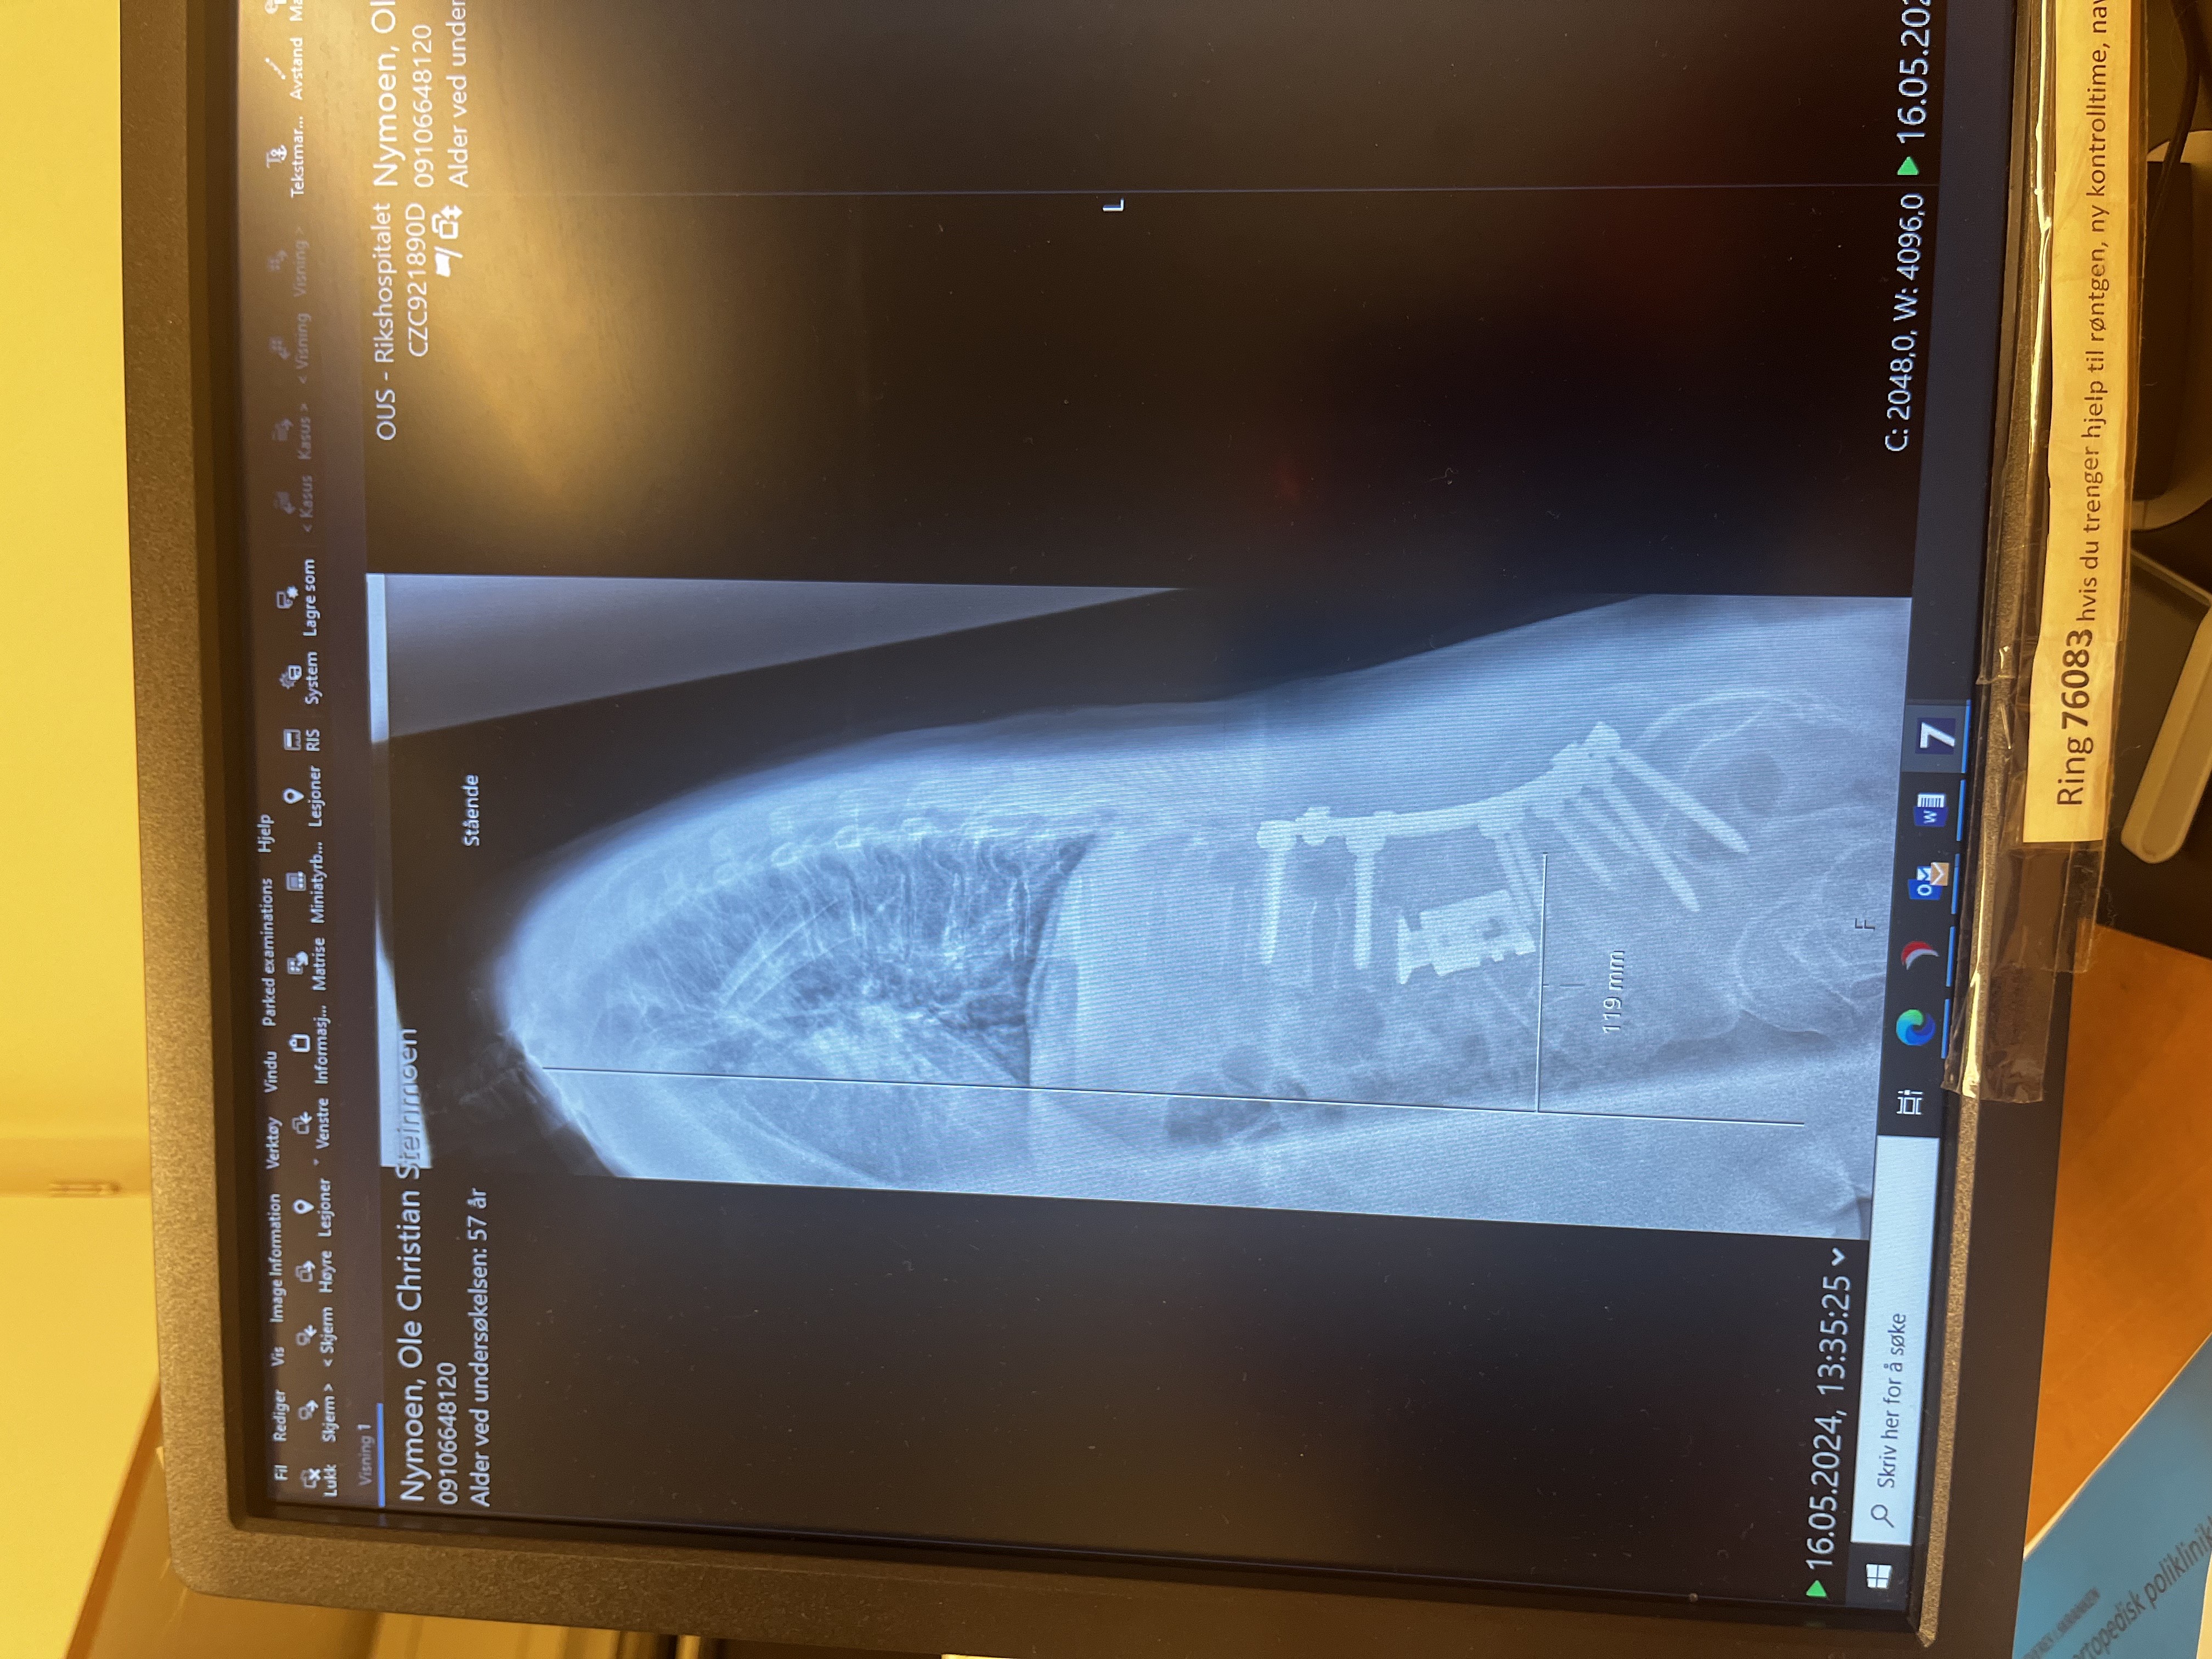

KUNSTVERKET: Titankoppen som erstatter rygghvirvelen er holdt fast av skruer og plater. Foto: Privat.

I Nymoens tilfelle sitter svulsten i ryggvirvelen L4, altså i nedre del av korsryggen.

Da de fjernet ryggvirvelen, en fire centimeter lang del av ryggsøylen, måtte de samtidig unngå å skade nærliggende nerver. Han ble snittet opp i magen og ryggen som et dyr på slaktebenken, og i buken brukte de en liten jekk for å få på plass en titankopp der ryggvirvelen satt.

Transplantert beinmarg rundt titanet skal nå gjøre at den vokser sammen med skjelettet.